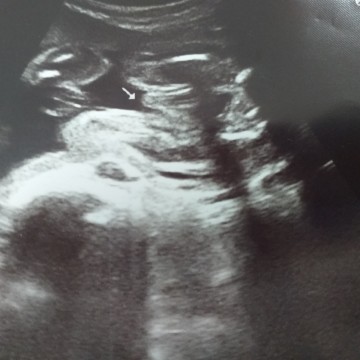

ผช ค่ะเห็นชัดมาก